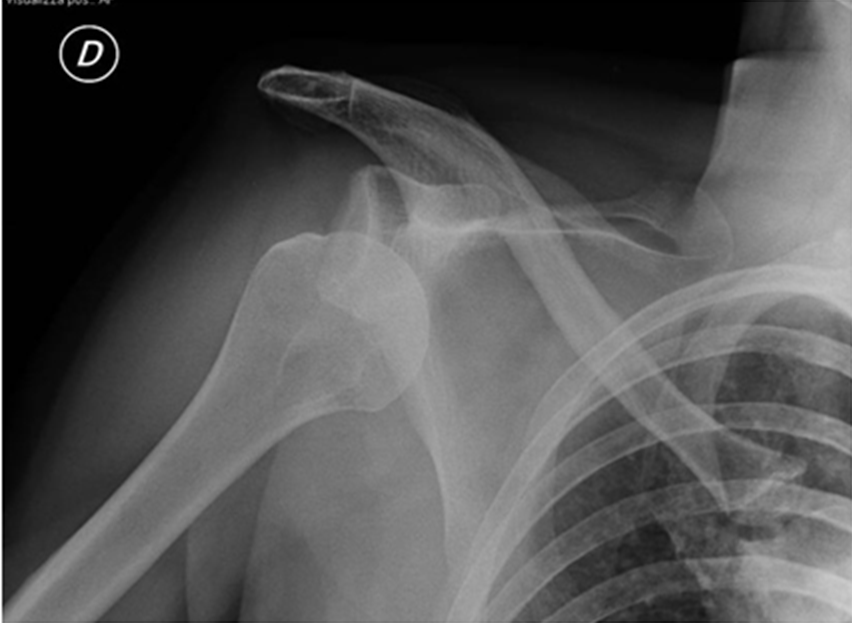

La spalla instabile può andare incontro a lussazione (fuoriuscita completa della testa omerale dal suo alloggiamento normale, glenoide della scapola), sublussazione (parziale fuoriuscita della testa omerale) o a dolore in particolari posizioni o movimenti dovuti a spostamenti anormali della testa omerale come in ripetuti gesti sportivi o lavorativi. Quando le lussazioni avvengono ripetutamente, anche a distanza di molto tempo, si parla di lussazione recidivante.

Nella scelta della tecnica di intervento influiscono diversi elementi: età, numero di lussazioni o, in assenza di queste, durata del dolore alla spalla e grado di impedimento durante l’attività sportiva o lavorativa, struttura muscolare, livello di carico durante il lavoro, pratica di sport o attività motorie a livello agonistico o amatoriale. Fondamentale è anche poter escludere la presenza di fratture associate alla lussazione e per questo un esame più approfondito con TAC o RMN può essere di grande utilità.